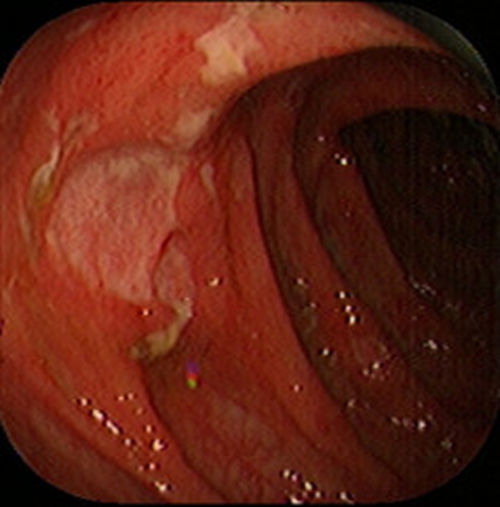

急性胃炎圖片

急性胃炎陽性表現

急性胃炎陽性的表現的

急性胃炎陽性的表現

急性胃炎陽性表現的

急性胃炎的陽性的表現的

急性胃炎的陽性的表現